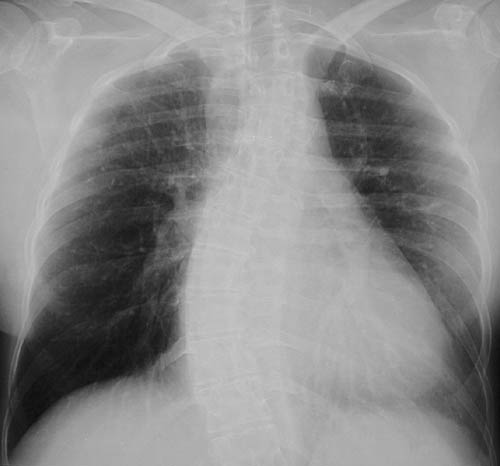

| The PA chest radiograph above and the lateral view below demonstrate cardiomegaly and prominent pulmonary arteries in a case of Eisenmenger complex. Eventually, failure of one ventricular chamber leads to failure of the other, and global enlargement, as in this case. Note that there is marked thoracic scoliosis. |